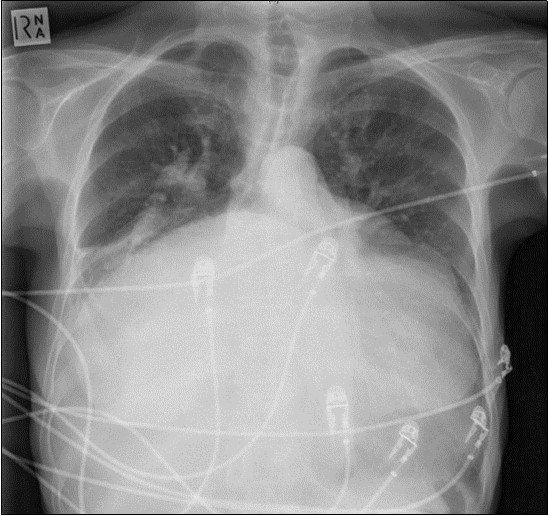

A 64-year-old woman was admitted to the Intensive Care Unit (ICU) after a medical emergency team (MET) call from the cardiology ward due to a reduced level of consciousness and respiratory distress. Past medical history included rheumatic fever as a child and chronic atrial fibrillation. She had been admitted to hospital 3 days previously with worsening shortness of breath. On observation she was drowsy but rousable to voice, with a respiratory rate of thirty breaths per minute. Examination revealed a raised jugular venous pressure, a pan-systolic murmur as well as a long mid-diastolic murmur, both loudest at the apex and radiating to the axilla, a soft first heart sound, a displaced tapping apex beat, and bi-basal medium-intensity inspiratory crepitations. Her electrocardiogram showed atrial fibrillation with a rapid ventricular response of 126 beats per minute. Her arterial blood gas demonstrated an acute on chronic respiratory acidosis with a pH 7.02, PaCO2 176 mmHg, and a HCO3- of 43 mmol/L. An antero-posterior (AP) chest x-ray on admission displayed cardiomegaly, splayed carina and hilar venous congestion, with a lateral film showing the left atrium occupying a significant part of the chest cavity (see Figure 1a, Figure 1b).

Figure 1a.Chest X-ray Antero-posterior view. Findings showing enlarged left atrium, splaying of the carina, hilar venous congestion